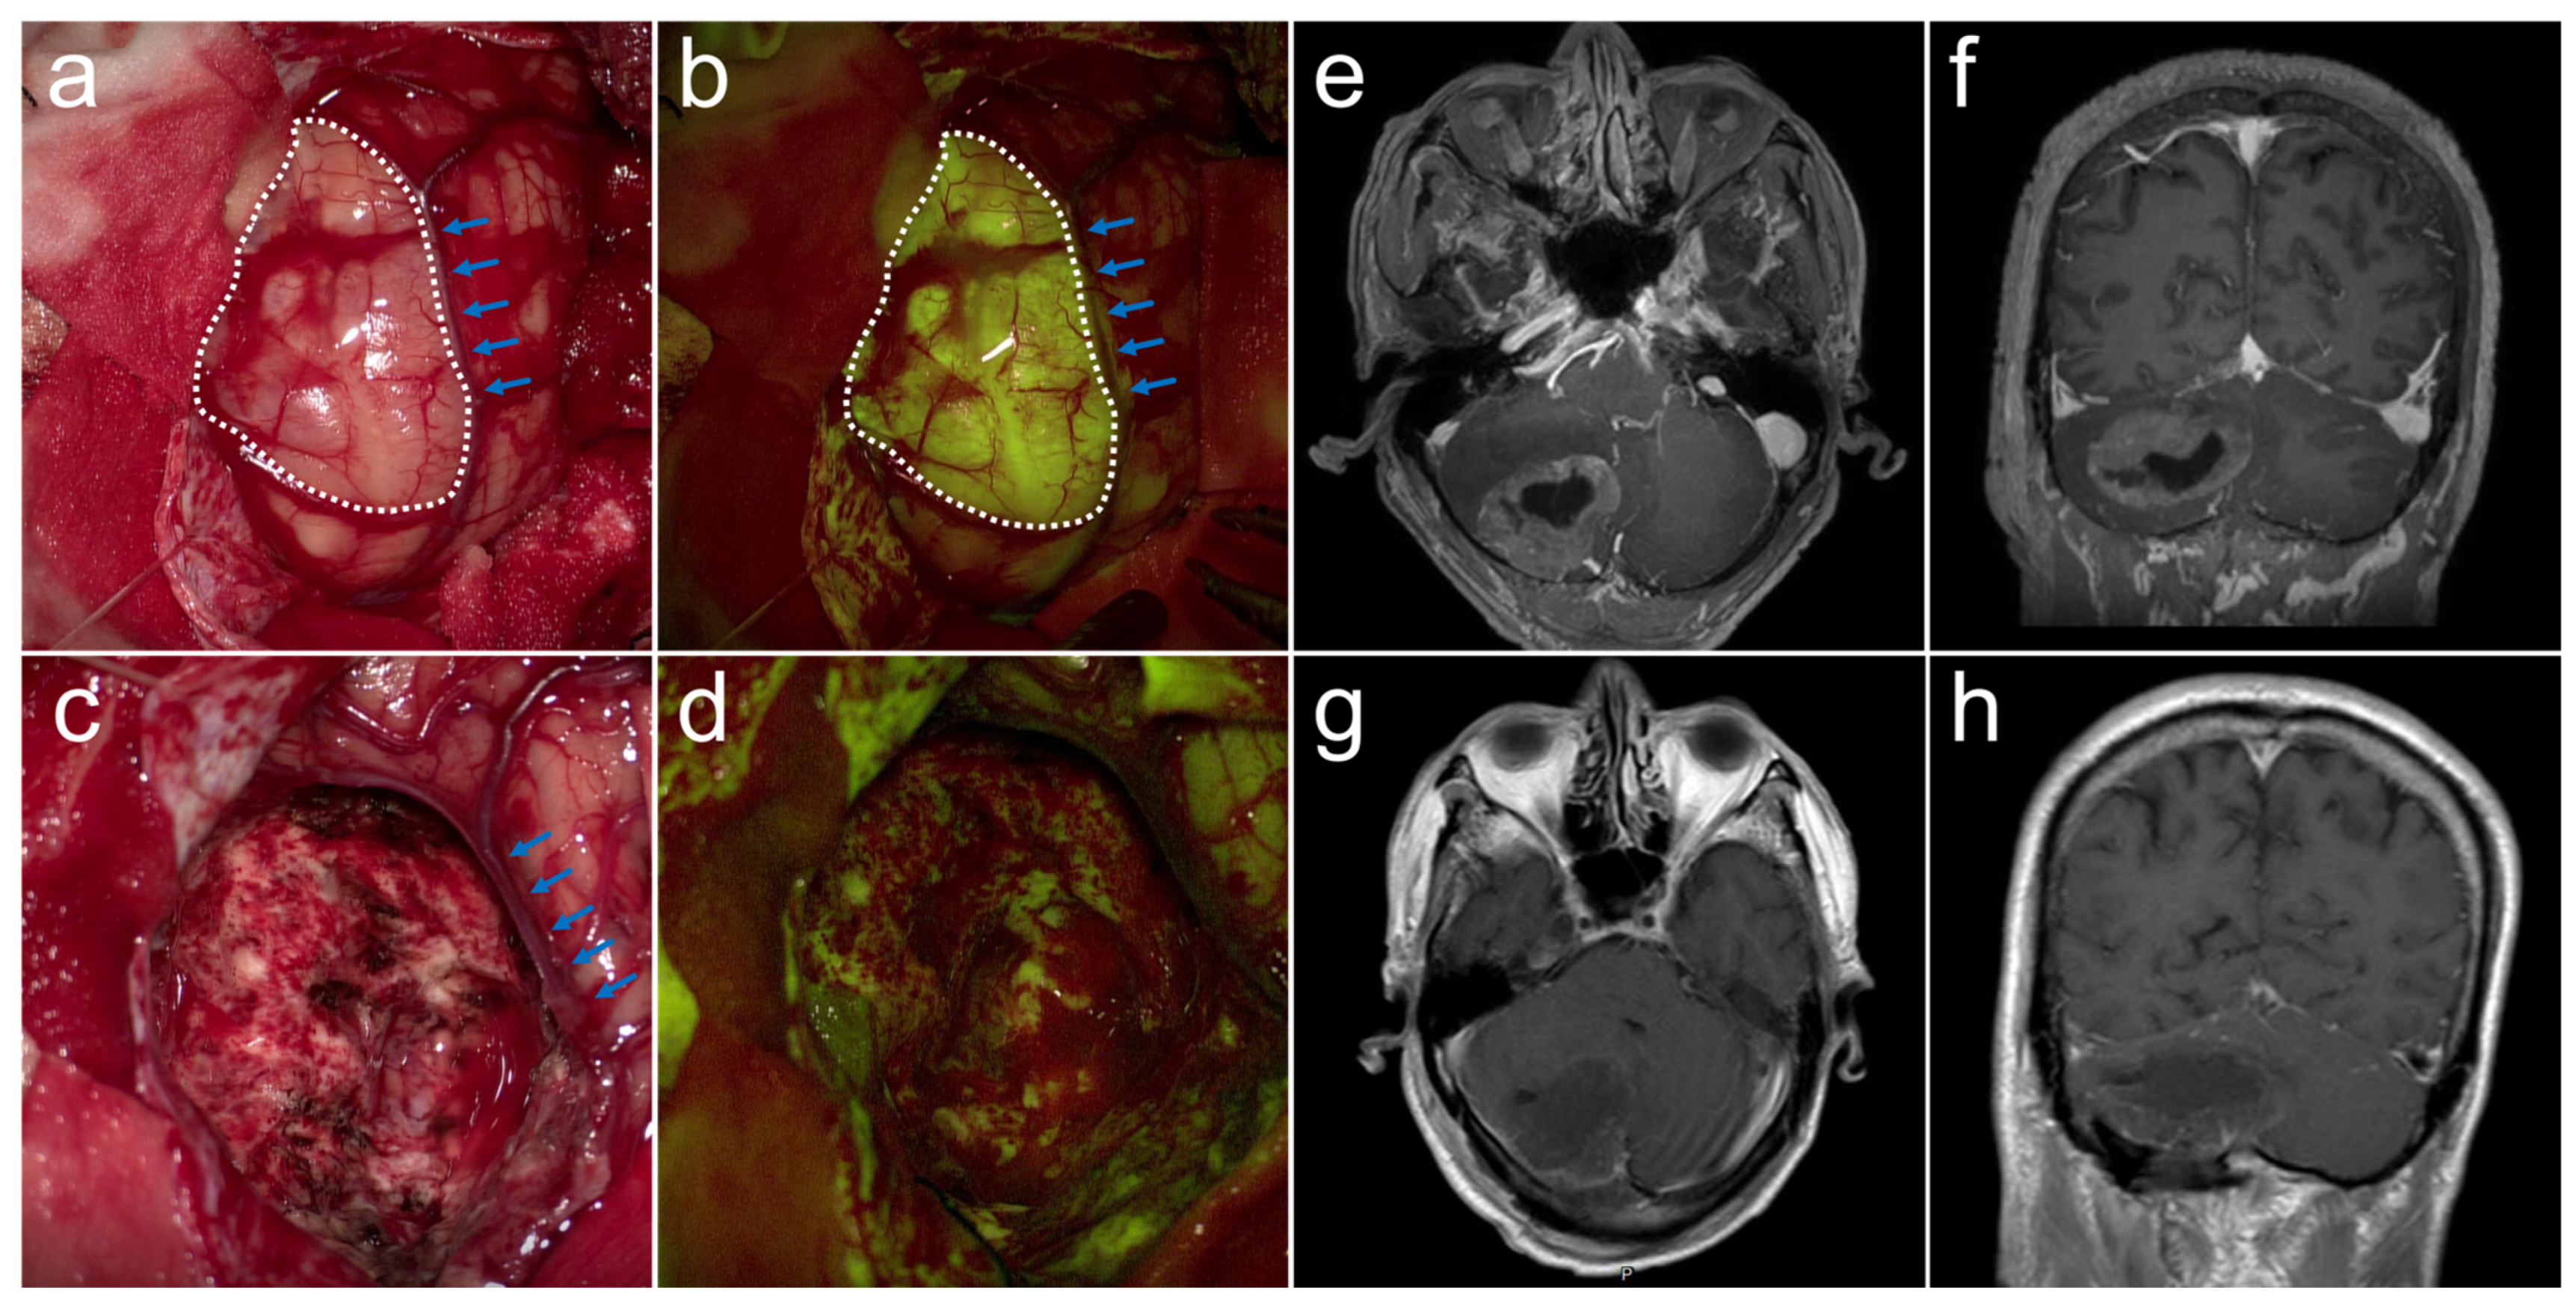

3.2. Fluorescence of BMs

3.3. Surgical Resection and Local Outcome